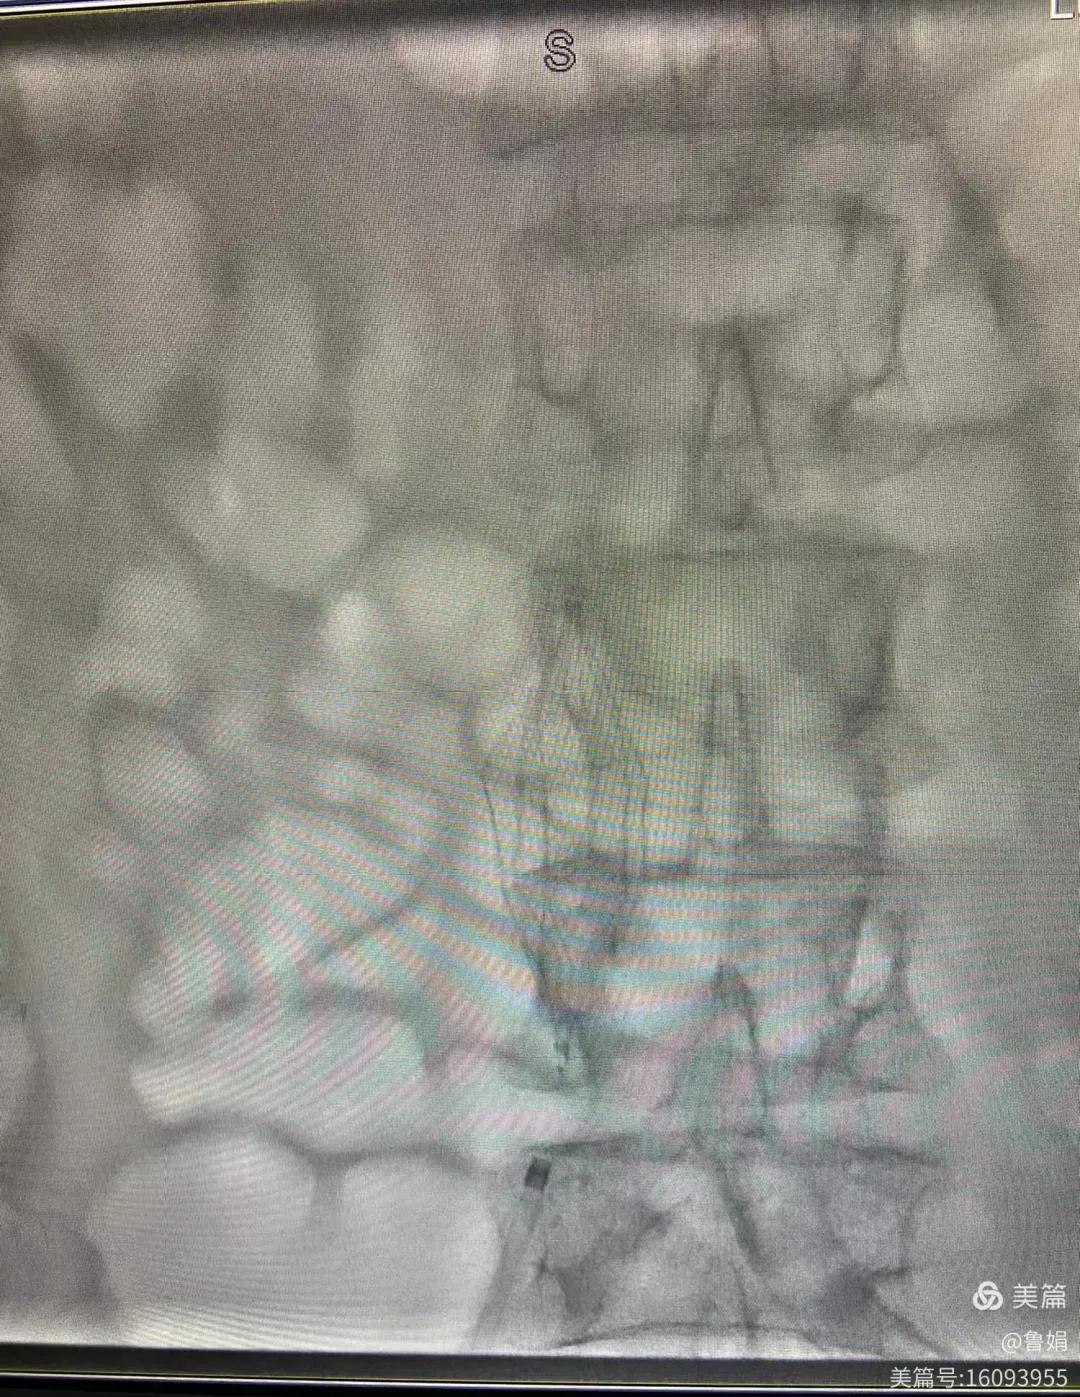

11月3日,漯河市中醫(yī)院血管外科副主任周創(chuàng)業(yè)與腦二科介入醫(yī)生孫亞中,兩位醫(yī)生為一位腦梗死伴下肢深靜脈血栓形成患者成功開展下腔靜脈濾器置入術(shù)。

圖片術(shù)后濾器順利植入

經(jīng)認(rèn)真查看患者病例,探討患者病情及術(shù)中潛在風(fēng)險(xiǎn)因素,多科會(huì)診后急診為患者開展介入手術(shù),術(shù)中周創(chuàng)業(yè)副主任、孫亞中副主任中醫(yī)師二人通力合作,手術(shù)順利,病人術(shù)中出血少,生命體征平穩(wěn),現(xiàn)在腦二科病房繼續(xù)對(duì)癥治療。(介入中心:魯娟)